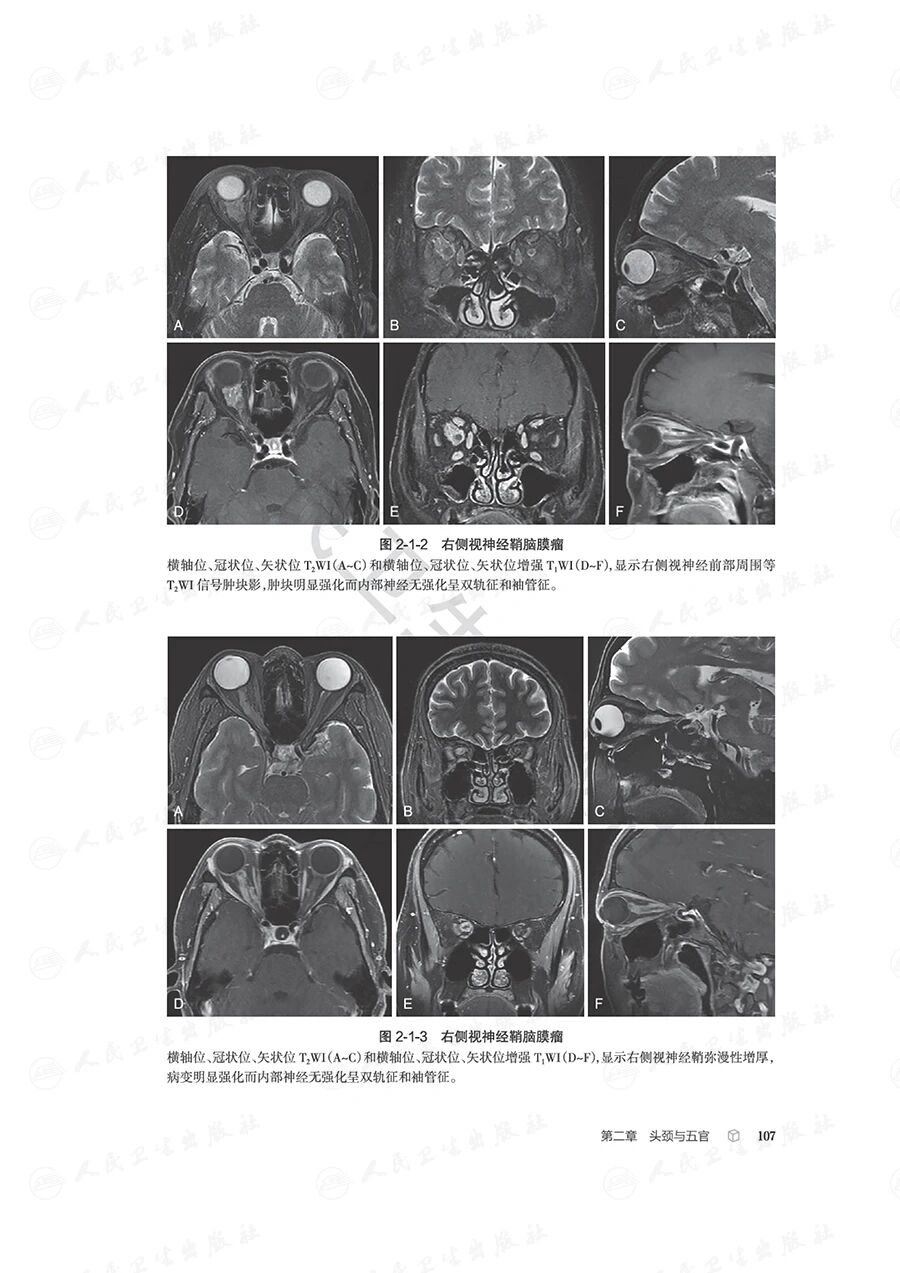

本书紧扣影像科医师日常执业场景,依托中华医学会放射学分会青年学组“青影智慧-影像诊断思维系列培训课程”的核心体系,全面汇总并梳理了临床影像诊断中高频出现的近300个典型征象,覆盖神经系统、头颈五官、呼吸、心脏大血管、乳腺、消化、泌尿、生殖、骨关节等九大核心诊疗领域。

全书以影像征象为核心切入点,深入剖析并提炼各征象的特异性影像学表现,辅以典型病例图像直观佐证;借助思维导图清晰可视化征象分析与诊断推导的完整脉络,同步融入鉴别诊断的关键要点及适配疾病谱系。通过层层拆解、去芜存菁的解析方式,完整呈现从影像征象识别到疾病确诊的全链条思维推演过程,为影像科医师提供极具参考价值的诊断思维范式。

本书旨在为医学专业人士提供系统化的影像诊断思维框架,涵盖了全身各个器官系统的常见疾病。每个章节不仅详尽介绍了各类疾病的影像学特征,还配有诊断思维树和鉴别诊断疾病谱,旨在帮助读者快速而准确地进行影像诊断。这种结构化的方法将使读者在处理复杂病例时更加得心应手。